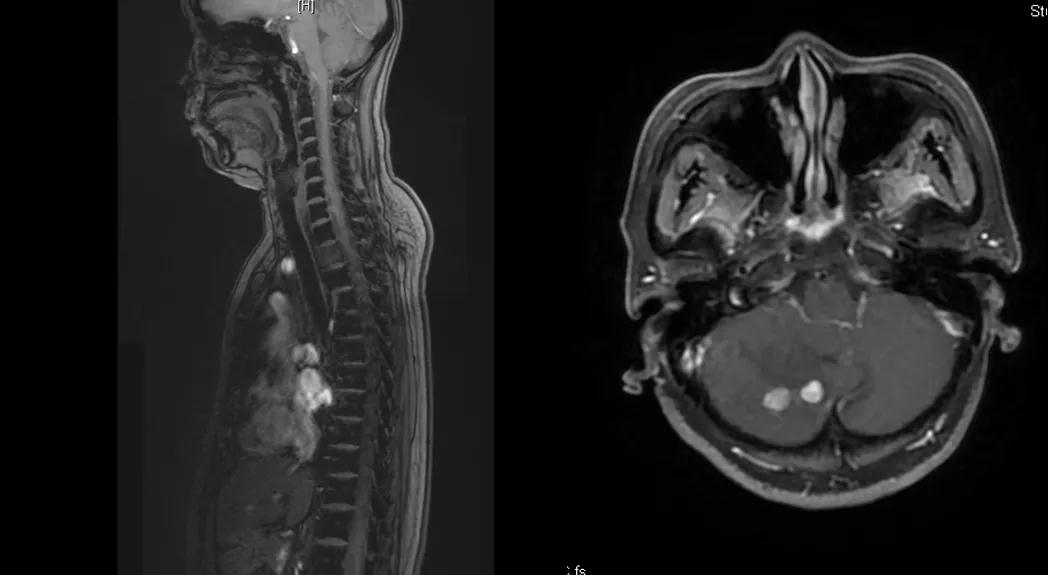

曲妥珠单抗辅助治疗结束6个月后,患者出现左侧胸部疼痛,ECT检查提示:左侧第4、5肋骨及T2胸椎转移;MR提示:T2椎体转移,肝S6段异常强化灶,考虑转移瘤可能性大;脑转移(图1)。

图1